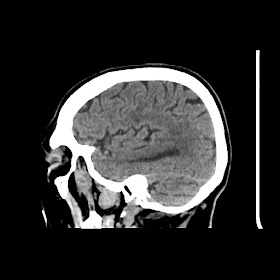

A 75 years old woman with DM-2 since 3 years

Patient O/E images:

C/O: Breathlessness X 2-3 day's

H/O: unconsiouness since few hour's at home around 10:30 pm

K/C: DM / HTN since 2-3 year's